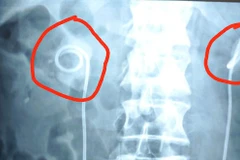

Theo chỉ định, sonde JJ cần được rút ra trong vòng 3 tháng, tuy nhiên, ông T. không đi tái khám để rút sonde vì cho rằng sức khỏe bình thường, dù được bác sỹ và gia đình nhắc nhở nhiều lần.